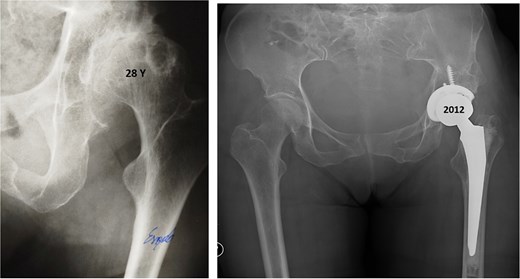

In 1984, a 35-year-old female patient presented to our department with severe left groin pain. Preoperative pelvic radiographs revealed acetabular dysplasia with subluxation at Crowe Grade I and Tönnis Grade I. A Pol Le Cœur corrective TPO was performed (Fig. 1). Over the following 28 years, radiographic examinations demonstrated progressive articular degradation despite the initial clinical success of the osteotomy.

Postoperative anteroposterior radiographs of the pelvis, showing Pol Le Cœeur triple pelvic osteotomy performed on a 35-year-old female patient to treat an acetabular dysplasia in the left hip, at Grade 1 Crowe’s classification.